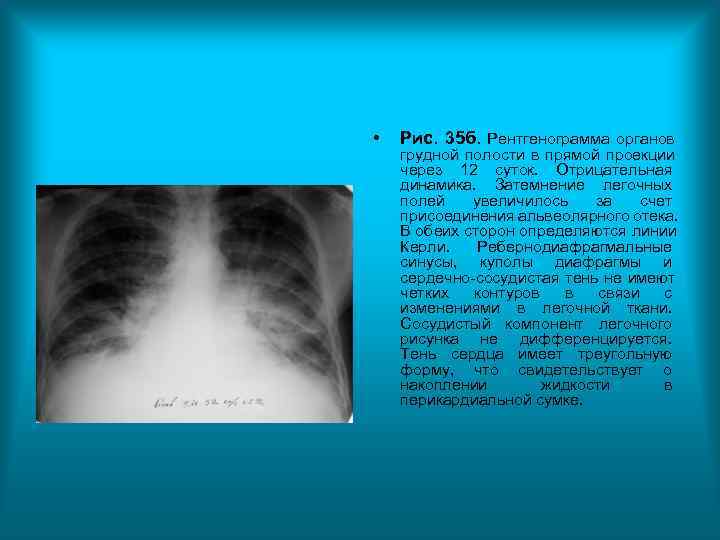

Пациент Б. 39 л. Диагноз: Инфаркт миокарда. • Рис. 35 а. Рентгенограмма органов грудной полости в прямой проекции. Легочные поля снижены в прозрачности за счет обогащения и деформации легочного рисунка. , который представлен широкими сосудами образующими извилистые тени. Хорошо дифференцируются вертикально ориентированные артериальные и горизонтально расположенные венозные сосуды. Междолевая плевра справа утолщена и деформирована, смещена книзу. Корни легких расширены и не структурны. Сердечно-сосудистая тень увеличена в размерах, дуги сердца хорошо визуализируются.

• Рис. 35 б. Рентгенограмма органов грудной полости в прямой проекции через 12 суток. Отрицательная динамика. Затемнение легочных полей увеличилось за счет присоединения альвеолярного отека. В обеих сторон определяются линии Керли. Ребернодиафрагмальные синусы, куполы диафрагмы и сердечно-сосудистая тень не имеют четких контуров в связи с изменениями в легочной ткани. Сосудистый компонент легочного рисунка не дифференцируется. Тень сердца имеет треугольную форму, что свидетельствует о накоплении жидкости в перикардиальной сумке.